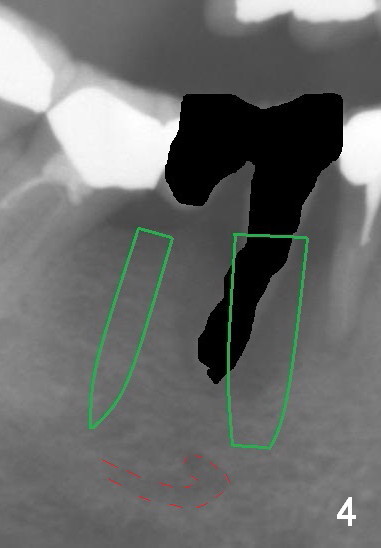

A 50-year-old lady (ZC) has poor dentition (Fig.1). The buccal gingiva of the tooth #29 is erythematous and edematous with deep pockets and severe bone resorption (Fig.2). Two units of the 5-unit bridge is going to be removed (Fig.3). A large implant is to be placed at the site of #29 (socket treated with Metronidazole), while a small one (probably 1-piece) at #30 (narrow mesiodistal space, Fig.4 green outlines). Be care of the mental loop (red dashed line). In fact, the patient wants to have #3 implant placed first.